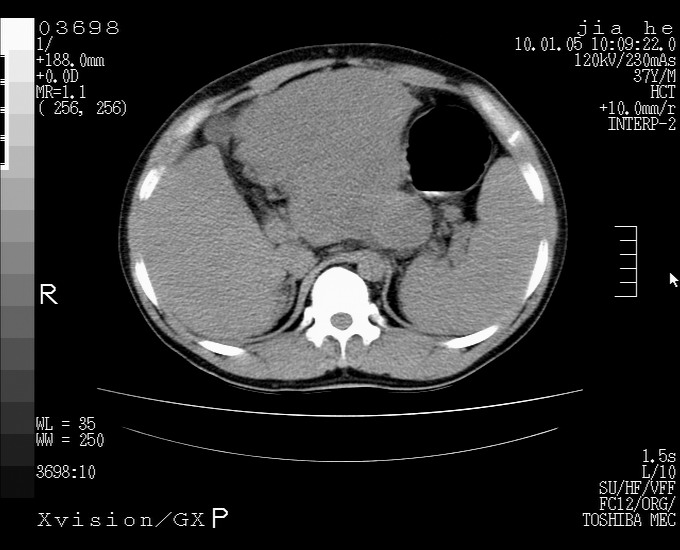

标题: CT23988:男,40岁,B超提示腹部肿物,请各位老师给看看。 [打印本页]

标题: CT23988:男,40岁,B超提示腹部肿物,请各位老师给看看。

左叶够大的,且与胰腺欠清晰,请增强扫描

考虑肝癌 请强化

肝癌并腹膜后淋巴西结转移

1.该患者有腹部手术史

2.脾大,肠系膜密度增高,有多发索条影,胰腺边缘毛糙,腹膜增厚,推测有肝硬化,门脉高压,腹膜炎和/或胰腺炎

3.肝左叶巨大站位,并腹腔淋巴结肿大,肝癌或肝间叶来源恶性肿瘤,也不排除大网膜间质瘤侵及肝左叶

建议:增强或磁共振

肝癌并腹膜后淋巴结转移

外生性肝癌并腹膜后淋巴西结转移!

考虑肝左叶外侧段癌并腹膜后淋巴结转移.建议增强进一步检查.